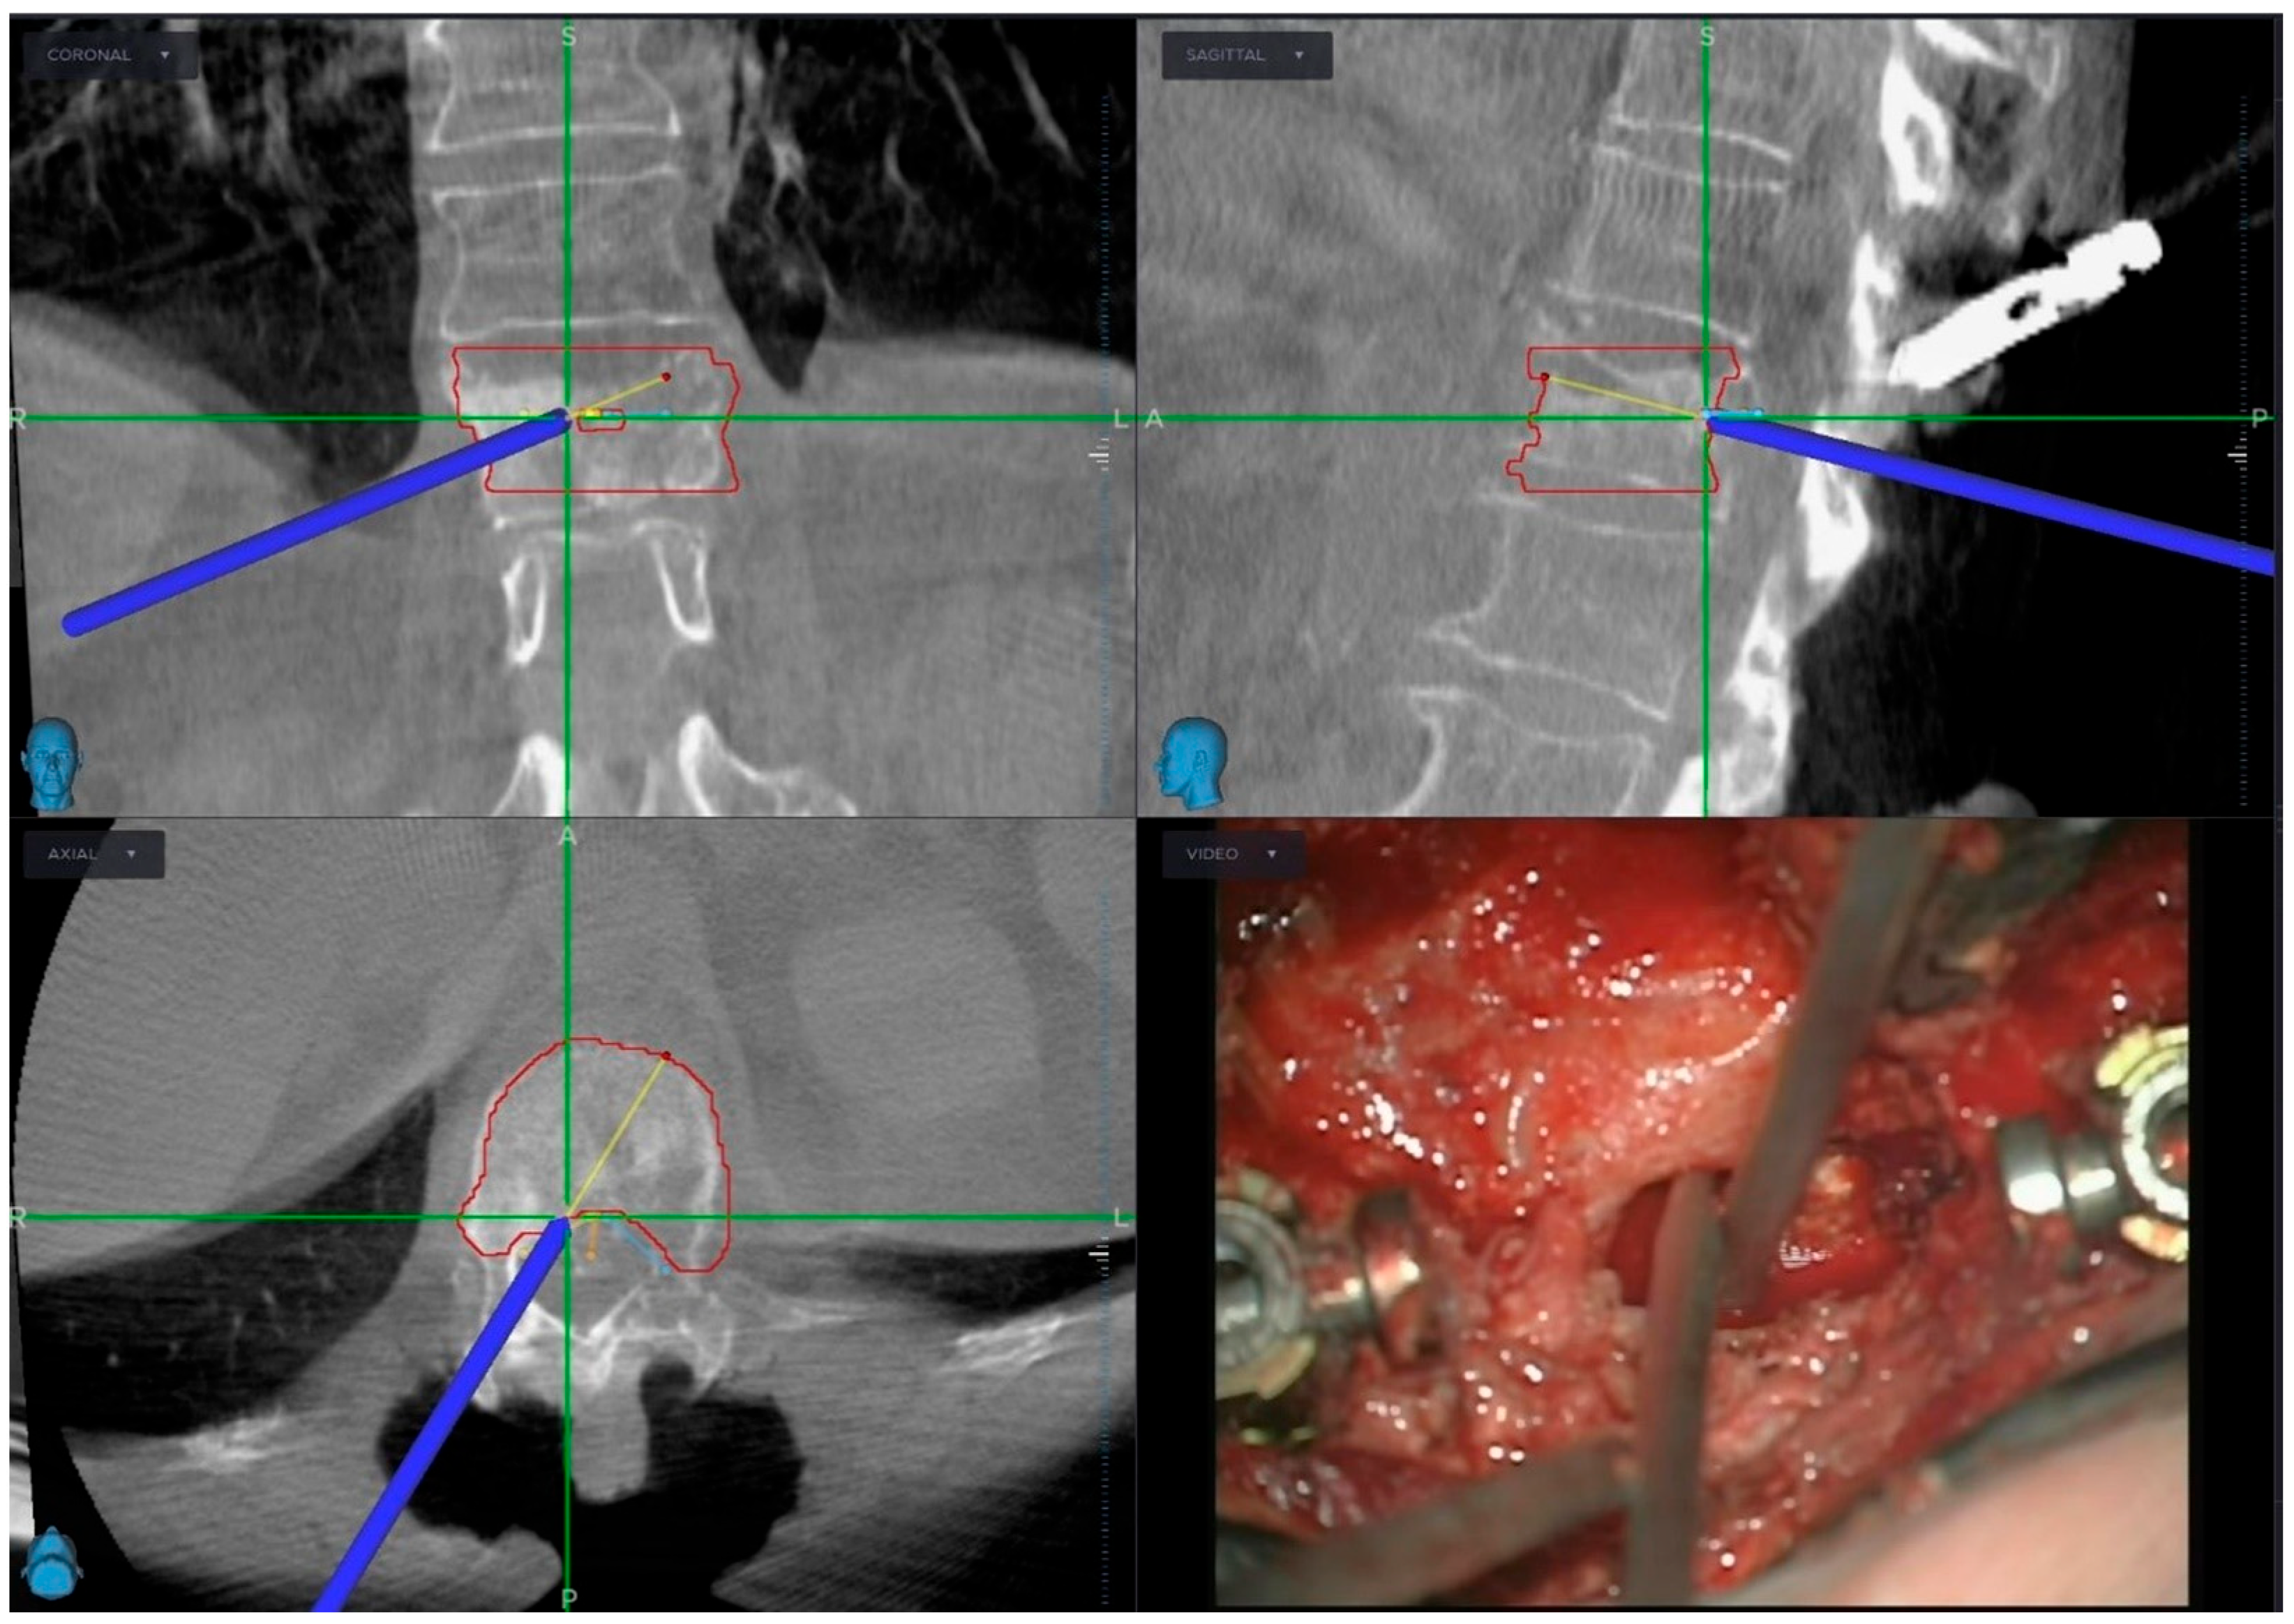

2.2. Pre-Operative Planning and Treatment Strategy

2.3. Radiotherapy Planning and Delivery